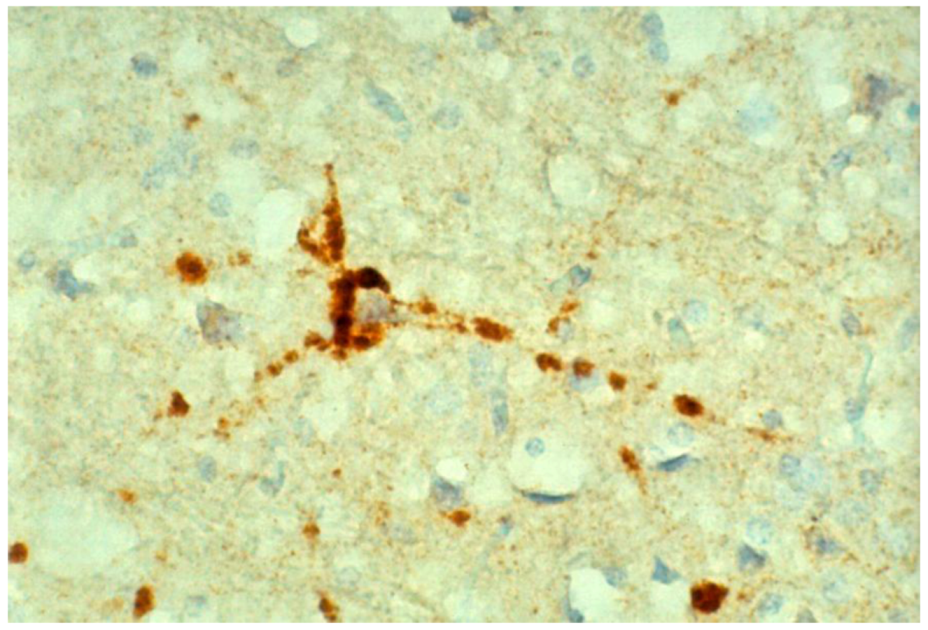

8. Neuropathology

- Piccardo, P.; Safar, J.; Ceroni, M.; Gajdusek, D.C.; Gibbs, C.J. Immunohistochemical localization of prion protein in spongiform encephalopathies and normal brain tissue. Neurology 1990, 40, 518–522. [Google Scholar] [CrossRef]

- Liberski, P.P.; Sikorska, B.; Lindenbaum, S.; Goldfarb, L.G.; McLean, C.; Hainfellner, J.A.; Brown, P. Kuru: Genes, cannibals and neuropathology. J. Neuropathol. Exp. Neurol. 2012, 71, 92–103. [Google Scholar] [CrossRef]

- Hainfellner, J.; Liberski, P.P.; Guiroy, D.C.; Cervénaková, L.; Brown, P.; Gajdusek , D.C.; Budka, H. Pathology and immunohistochemistry of a kuru brain. Brain Pathol. 1997, 7, 547–554. [Google Scholar] [CrossRef]

- McLean, C.A. The neuropathology of kuru and variant Creutzfeldt-Jakob disease. Phil. Trans. R. Soc. 2008, 363, 3685–3687. [Google Scholar] [CrossRef]

- McLean, C.A.; Ironside, J.W.; Alpers, M.P.; Brown, P.W.; Cervenakova, L.; Anderson, R.M.; Masters, C.L. Comparative neuropathology of kuru with the new variant of Creutzfeldt-Jakob disease: Evidence for strain of agent predominating over genotype of host. Brain Pathol. 1998, 8, 428–437. [Google Scholar]